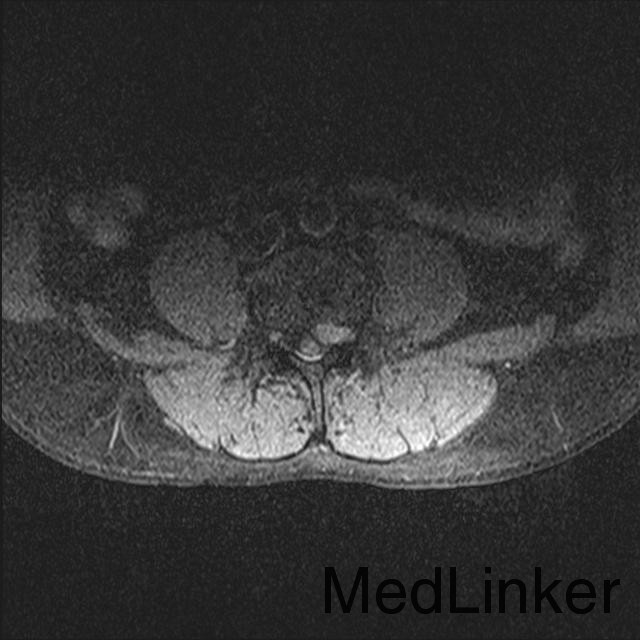

游离型腰椎间盘突出症的手术治疗

腰痛伴右下肢疼痛一周

查体 辅查

腰椎前屈受限,腰34,45右侧棘突旁压痛,放射痛(+),右下肢直腿抬高试验阳性,右小腿皮肤感觉减退

诊断 处理

腰椎间盘突出(游离型) 腰后路减压+髓核摘除椎间融合+植骨内固定

随访 讨论

1.游离型髓核是否可以被吸收 2.手术时机如何把握 3.是否需要融合